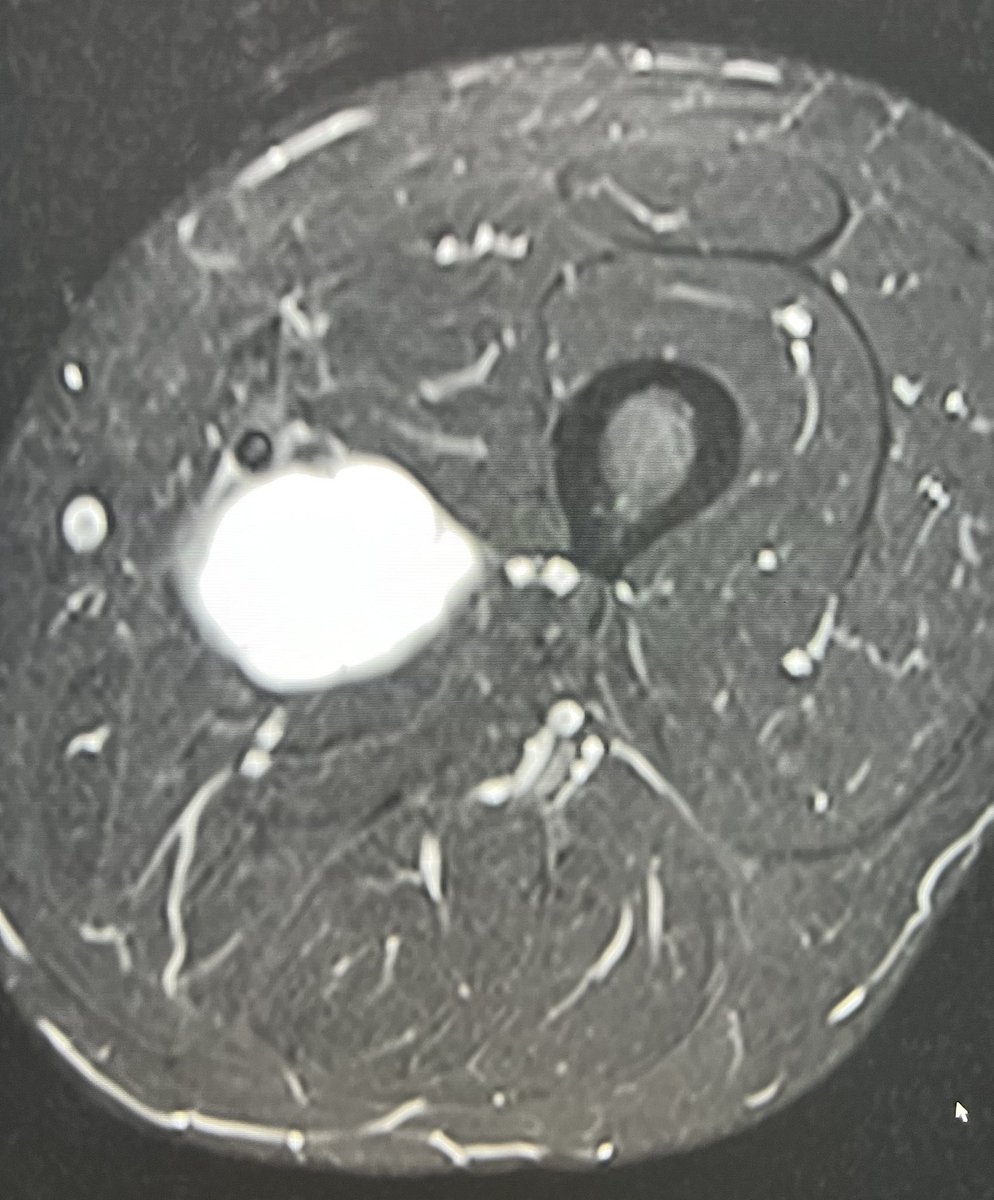

11 yo male with history of growth retardation and myopia presents with bradycardia and loss of consciousness.

Tumefactive perivascular spaces containing an ICA aneurysm.

#radres #FOAMed #neurotwitter #Neurology #Neurosurgery